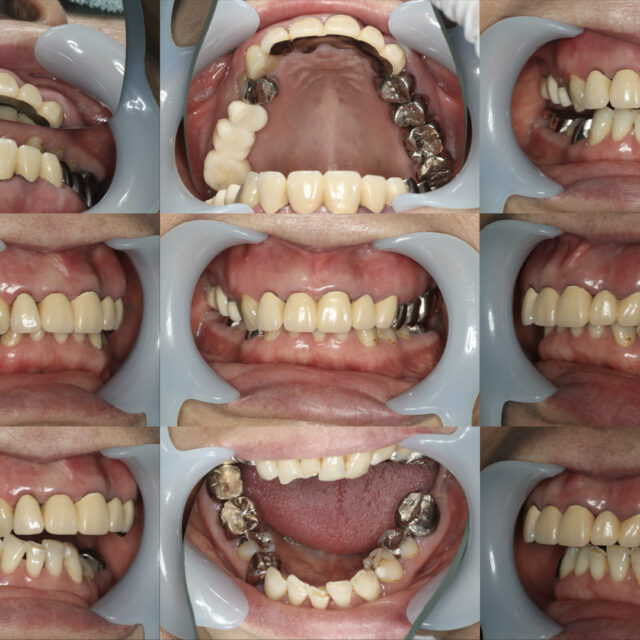

久しぶりの投稿。●症例投稿●全顎治療・咬合治療・咬合再構成002

- 2022年11月16日

- セラミック,咬合治療/フルマウス/咬合再構成,矯正治療